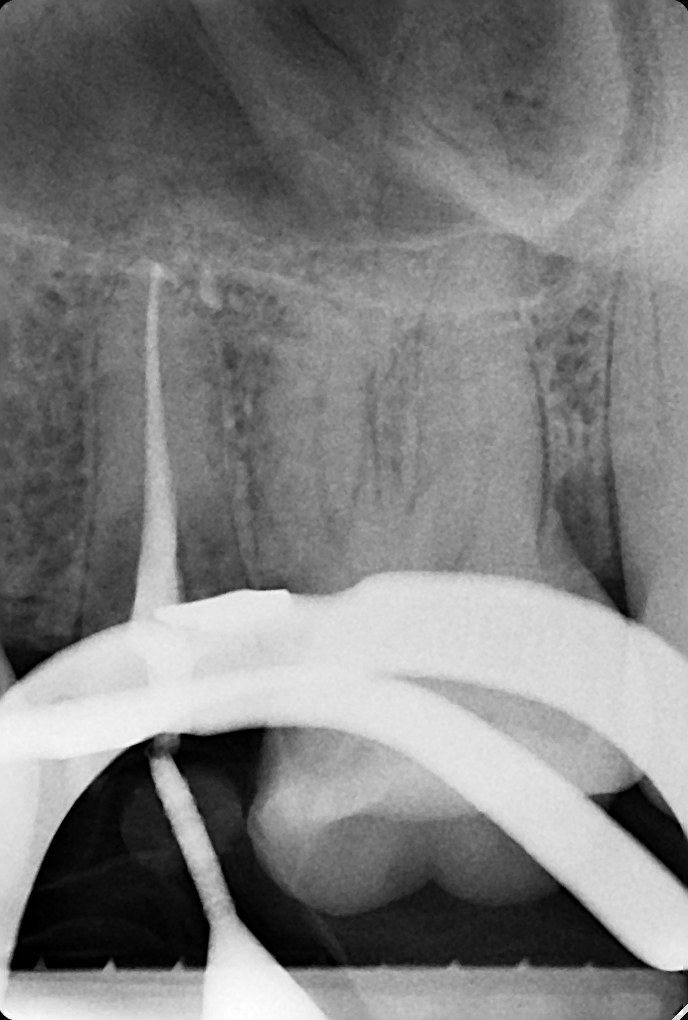

Клинические случаи в эндодонтии